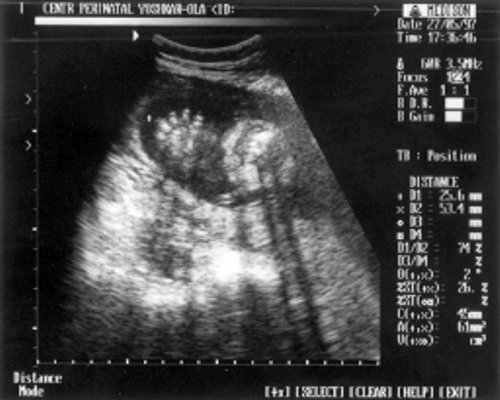

- ДБ (длина бедра) = 24 мм - 17 нед. (рис. 2)

- Плечевая кость = 16 мм - 14,5 нед. (рис. 3)

- Кости предплечья = 17,5 мм - 15,5 нед. (рис. 4)